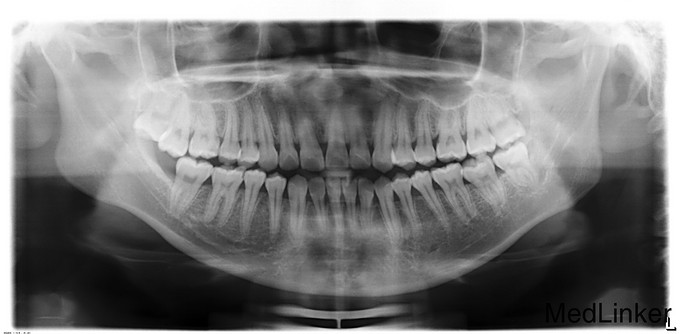

正颌术后半年余,患者2015年1月12日因“下颌偏斜10余年”来我院治疗,于2015年1月16日行“双侧下颌骨升支矢状劈开截骨前徙术+去骨皮质术+骨内坚固内固定术+上下颌牵引钉植入术”,今为取出下颌骨存留钛板来我院就诊,门诊以"正颌术后钛板存留"收入

双侧颜面部基本对称,下颌稍左偏,侧面观下颌稍突,双侧颞下颌关节区无弹响、压痛,双侧髁突活动度正常。开口度3.5cm,开口型“↘”。口内检查:全口恒牙列,口腔卫生一般,上下牙列中线不对齐,下牙列稍左偏,前牙对刃合。

诊断:正颌术后钛板留存,患者入院后完善相关检查,排除手术禁忌证,有手术指征,于2015年8月16日局麻下行“双侧下颌骨钛板钛钉取出术”,术后予消肿等对症治疗。